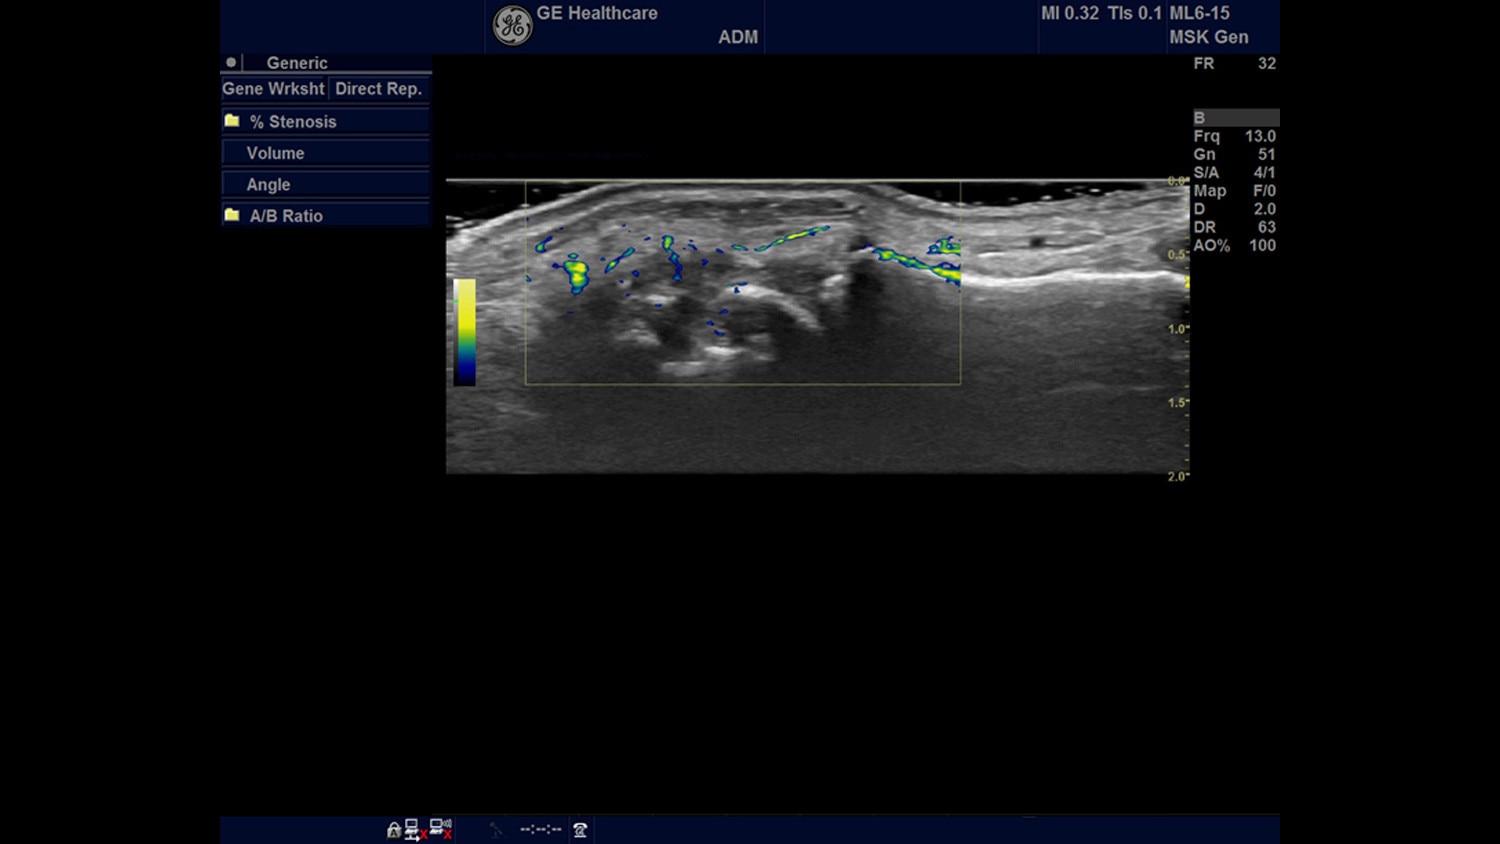

Welcome to GE Healthcare's dedicated website for rheumatology! GE is pleased to provide you with a one-stop access to clinically relevant information that can help you successfully incorporate ultrasound into your clinic or practice, or continue your search for topics to help advance your knowledge. For example, quantitative tools, like the one you see on the image to the right, are part of GE's comprehensive set of advanced tools for rheumatology to help you detect synovitis.